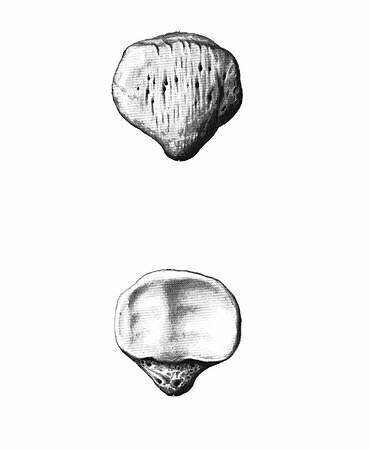

Хорошая картинка с изображением большеберцовой кости со всех сторон, в т.ч. сверху и снизу. Из интернета.

Проксимальный эпифиз сформирован медиальным и латеральным мыщелками, на которых расположены суставные поверхности, образующие большеберцовую часть коленного сустава. Между суставными поверхностями есть костные площадки - переднее и заднее межмыщелковые поля, к которым крепятся передняя и задняя крестообразные связки соответственно (внутренние связки коленного сустава).

В области медиального мыщелка находится точка крепления полуперепончатой мышцы.

Сбоку латерального мыщелка находится суставная поверхность проксимального (верхнего) межберцового сочленения (сустав с малоберцовой костью).

На задней поверхности зпифиза находится точка крепления подколенной мышцы.

По передней поверхности посередине, под мыщелками находится бугристость большеберцовой кости - костный ориентир, точка опоры (при опоре на колено), а также точка крепления одного из крупнейших сухожилий - собственной связки надколенника, также с медиальной стороны к ней подходит общее сухожилие полусухожильной, тонкой и портняжной мышц (так называемая гусиная лапка, о которой много знают те, у кого были травмы коленного сустава). С этой бугристостью связано немало проблем у юных спортсменов, об этом будет статья.

Важные элементы большеберцовой кости.

Передняя поверхность большеберцовой кости - гребень. Очень хорошо прощупывается под кожей. Кто хоть раз ударялся этим местом отлично помнит это место.

Нижний эпифиз сформировон медиальной лодыжкой - тоже костный ориентир. Косточка с внутренней стороны голеностопного сустава. Этим местом тоже больно ударяться, и тут может быть перелом или ушиб (при подворачивании стопы).

К медиальной лодыжке крепятся медиальная группа связок надтаранного сустава (дельтавидные связки).

С внутренней стороны располагается суставная поверхность дистального (нижнего) межберцового сочленения.

Нижняя плоскость большеберцовой кости - суставная поверхность надтаранного чустава. В этом месте осевая нагрузка с таранной кости почти полностью передаётся на большеберцовую.